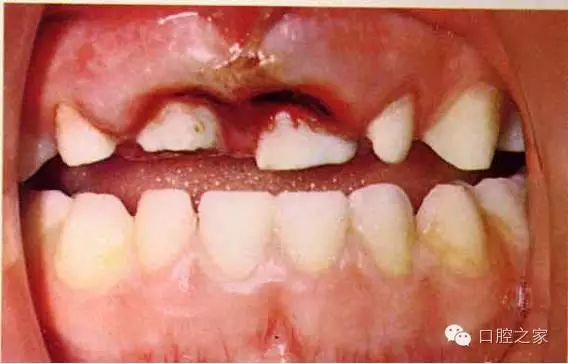

二、診斷

1.外傷史

2.臨床檢查:視診(缺損、色澤、移位、出血、牙齦)

觸診(動(dòng)度、疼痛)

叩診(疼痛、音調(diào))

牙髓檢查(活力)

3.X線檢查: 牙折、骨折、牙周組織、鄰牙、牙胚、

牙根形成及吸收等)